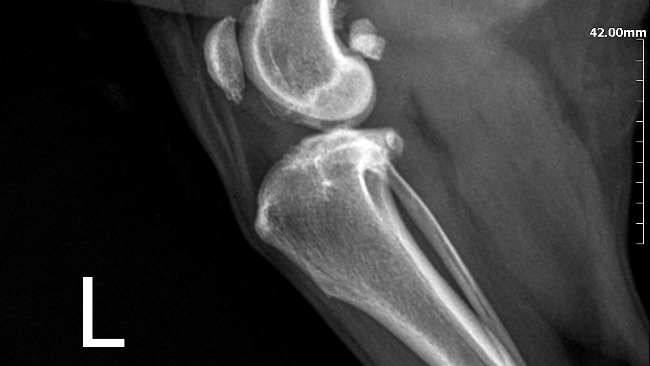

Kochani moje potrzeby schodzą na drugi plan. Moja sunia potrzebuje waszej pomocy. Eti musi przejsc operacje oraz leczenie, na które mnie niestety mnie niestac. Mogę jeździć na starym wózku, ale moi członkowie rodziny są dla mnie najważniejsi. Jestem gotowa zrezygnowac ze wszystkiego by jej pomóc.